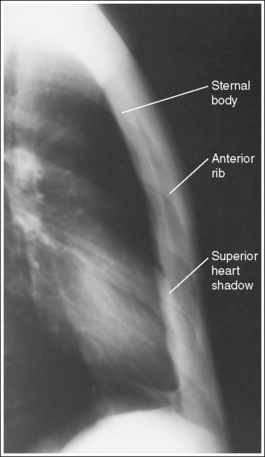

• Blurring overlying sternal structures. The SID recommended for the PA oblique sternum varies among positioning textbooks. It ranges from 30 inches (76 cm) to 40 inches (100 cm). A short (30-inch) SID provides increased magnification and blurring of the posterior ribs and left scapula but also results in a higher patient entrance skin dosage. Facility protocol dictates the SID. Using a breathing technique, which requires a long exposure time (3 to 4 seconds) and requires the patient to breathe shallowly (costal breathing) during the exposure, forces upward and outward and downward and inward movements of the ribs and lungs, thus blurring the posterior ribs and lung markings on the image. Deep breathing requires movement (elevation) of the sternum to provide deep lung expansion and should be avoided during breathing technique because this sternal motion would blur the sternum on the image (see Image 2).

IMAGE 2

If breathing technique is not used, the details and cortical outlines of the posterior ribs, left scapula and lung markings are sharply defined, and the increased recorded detail obscures the details of the sternum (see Image 3).

IMAGE 3

The patient was positioned in an LAO position. The thoracic vertebrae are superimposed over the heart shadow, and the sternum is demonstrated to the right of the heart shadow.

The right SC joint is sharply defined, but the sternal body, posterior ribs, and lung markings are blurry. Breathing technique was used for this image, but the patient was breathing deeply instead of shallowly, causing the sternum to move and blur.

The lung markings, posterior ribs, and left scapula are demonstrated without magnification or blurring, making it difficult to distinguish the sternum through these overlying structures. The SID was not shortened, and the patient's breathing was halted for this image. Also, patient obliquity was excessive, as indicated by the position of the sternum to the left of the heart shadow and by the amount of sternum rotation.

Shorten the SID to 30 inches (76 cm) if it is your facility's protocol, take the exposure while the patient is breathing shallowly, and decrease the degree of patient obliquity.